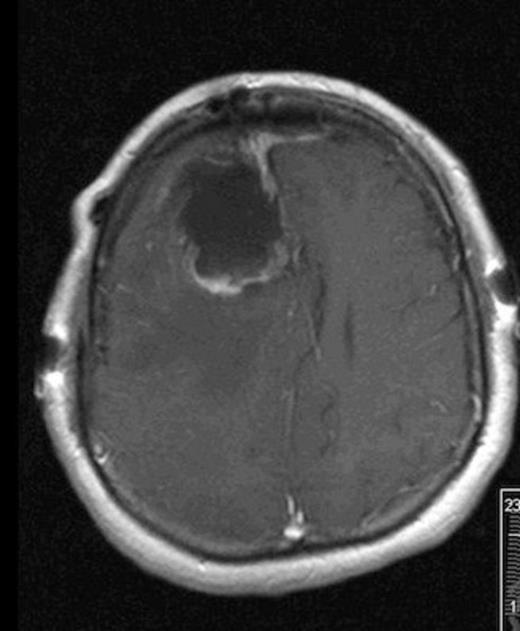

Our patient is a forty-nine year-old Native American female with a two-month history of progressively worsening headaches along with gait instability. She reported falling to the left side quite often. She presented to an outside hospital where CT scan of the head showed a large right frontal hypodense mass with significant vasogenic edema and twenty millimeters of left to right midline shift. She was transferred to University of New Mexico Medical Center where MRI of the brain demonstrated a 6.5 cm x 5 cm heterogeneously enhancing cystic and solid mass with significant vasogenic edema and midline shift (Fig 1). Her haematocrit was within normal limits at 40. Family history was negative for von Hippel Lindau Syndrome. VHL Genetic workup was negative and CT abdomen was negative for other lesions.

Axial MRI with contrast showing heterogenous enhancing solid and cystic component of tumor

Post-operative MRI showing gross-total resection with some residual blood in cavity